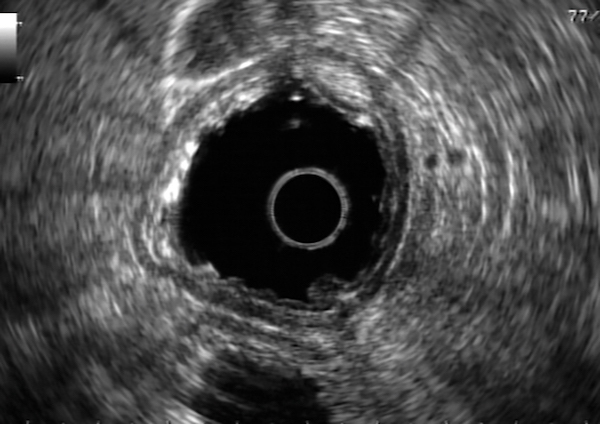

presented with worsening epigastric abdominal pain. He underwent an upper endoscopy, which showed a submucosal lesion in the gastric cardia as shown in FIGURE A. Subsequent endoscopic ultrasound (EUS) exam showed an intramural lesion arising from the muscularis propria measuring 35 mm x 28 mm. EUS-guided FNA [FIGURE B] showed a spindle cell tumor, positive for CD117 and DOG-1 on immunocytochemical assay. What is the next step in the management of this patient?

This case describes a GIST greater than 2 cm in size, confirmed with FNA and immunocytochemical assay. Followup management is thus required. Submucosal lesions <1 cm with EUS findings suggestive of benignity may be followed conservatively with EUS in 6 to 12 months, but would not be appropriate here due to the size of lesion. The management of lesions between 1 and 2 cm is controversial, with varied guidelines. Some clinicians will resect tumors between 0.5 and 1.0 cm in size by endoscopic snare resection. However, complete surgical resection is recommended for gastric GISTs >2 cm per NCCN guidelines due to risk or recurrence and metastatic spread, and would be the next best step for this patient.